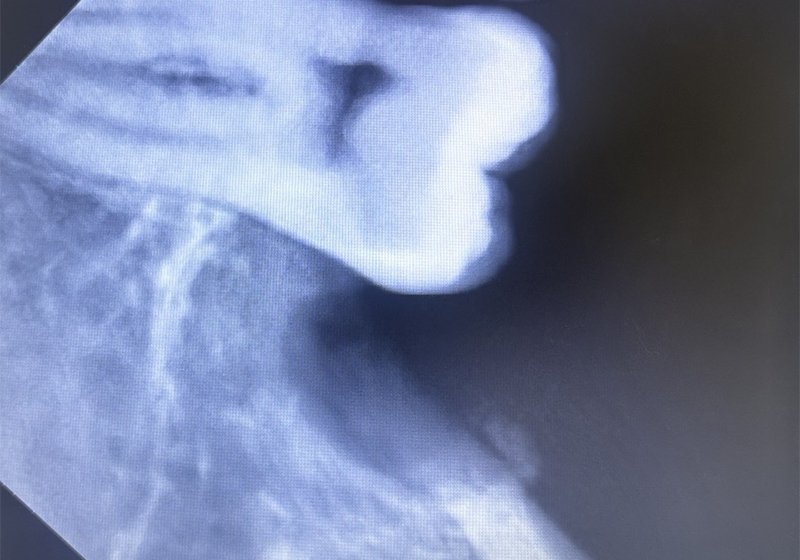

Wisdom tooth extraction

After: